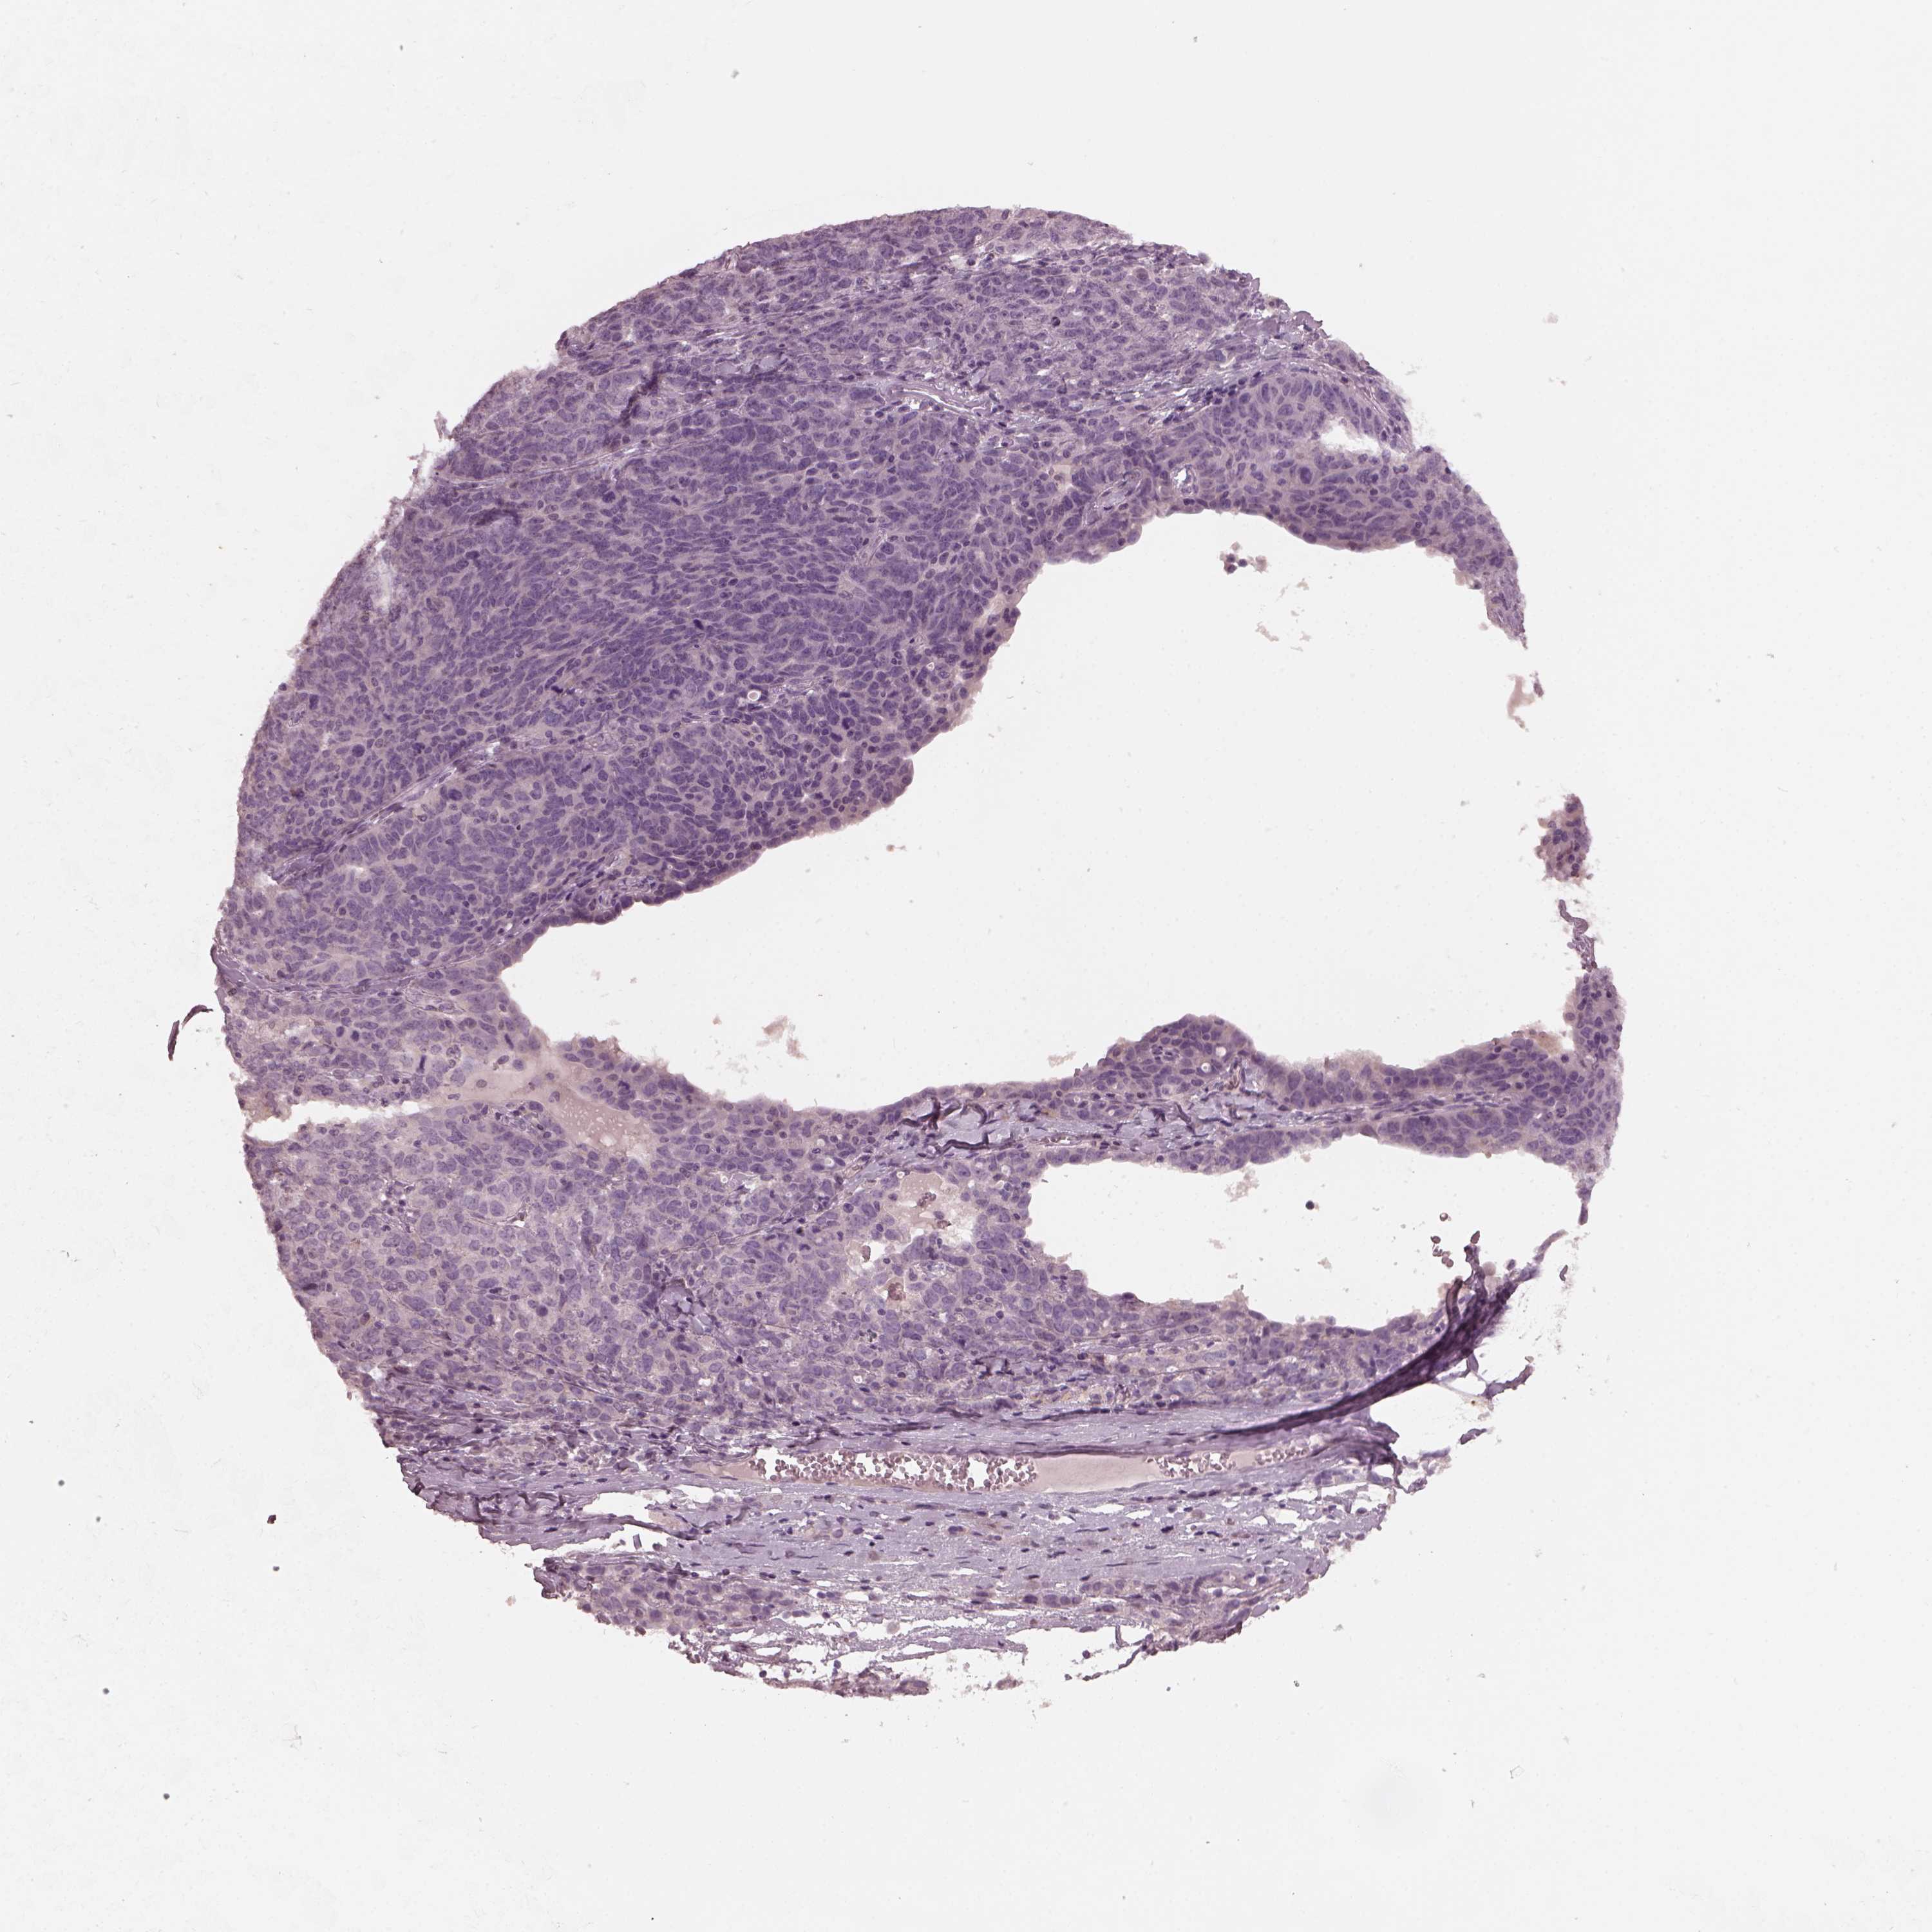

OVARIAN CANCER - Protein expressioni

A mouse-over function shows sample information and annotation data. Click on an image to view it in a full screen mode. Samples can be filtered based on level of antibody staining by selecting one or several of the following categories: high, medium, low and not detected. The assay and annotation is described here.

Note that samples used for immunohistochemistry by the Human Protein Atlas do not correspond to samples in the TCGA dataset.

Antibody stainingi

Antibody staining in the annotated cell types in the current human tissue is reported as not detected, low, medium, or high, based on conventional immunohistochemistry profiling in selected tissues. This score is based on the combination of the staining intensity and fraction of stained cells.

Each image is clickable and will lead to virtual microscopy that enables deeper exploration of all samples and also displays staining intensity scores, fraction scores and subcellular localization as well as patient and tissue information for each sample.

Antibody HPA015783

Antibody CAB022363

Cystadenocarcinoma, serous, NOS

Cystadenocarcinoma, mucinous, NOS

Carcinoma, endometroid